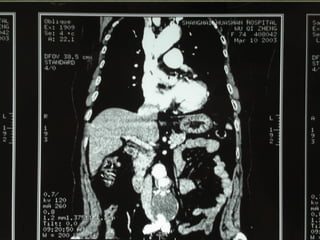

VR MPR MIP

10/20/15山血管外科网华 www.vascularcenter.cn 80

10/20/15山血管外科网华 www.vascularcenter.cn 81

10/20/15山血管外科网华 www.vascularcenter.cn 82

10/20/15山血管外科网华 www.vascularcenter.cn 84